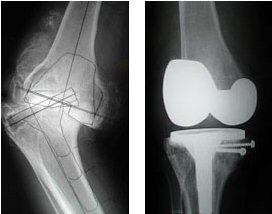

The lives of some elderly people are rendered miserable by progressive bow-leg deformity brought on by arthritic destruction of both knee joints.

Total knee replacement offers a chance for a return to a near normal life, but can be demanding on the surgeon when the condition has been allowed to progress to extremes.